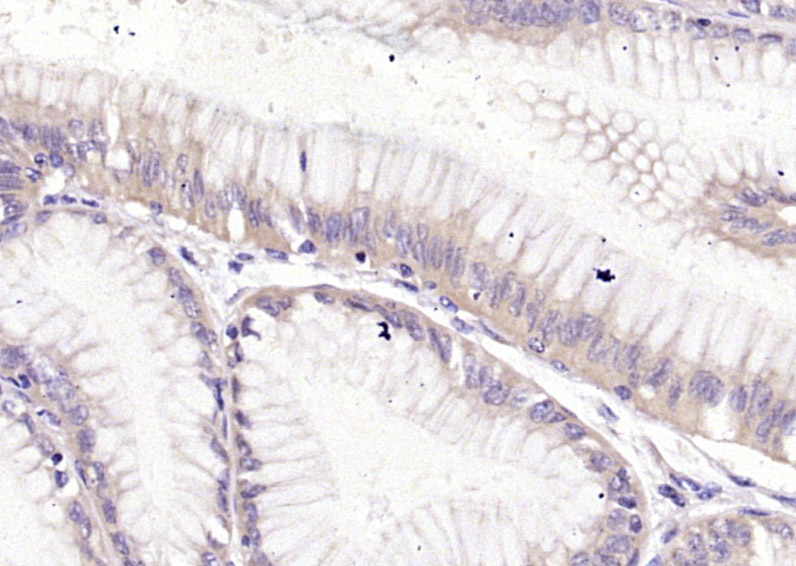

Paraformaldehyde-fixed, paraffin embedded (human gastric carcinoma); Antigen retrieval by boiling in sodium citrate buffer (pH6.0) for 15min; Block endogenous peroxidase by 3% hydrogen peroxide for 20 minutes; Blocking buffer (normal goat serum) at 37°C for 30min; Antibody incubation with (HRH2) Polyclonal Antibody, Unconjugated (bs-6664R) at 1:400 overnight at 4°C, followed by operating according to SP Kit(Rabbit) (sp-0023) instructionsand DAB staining.